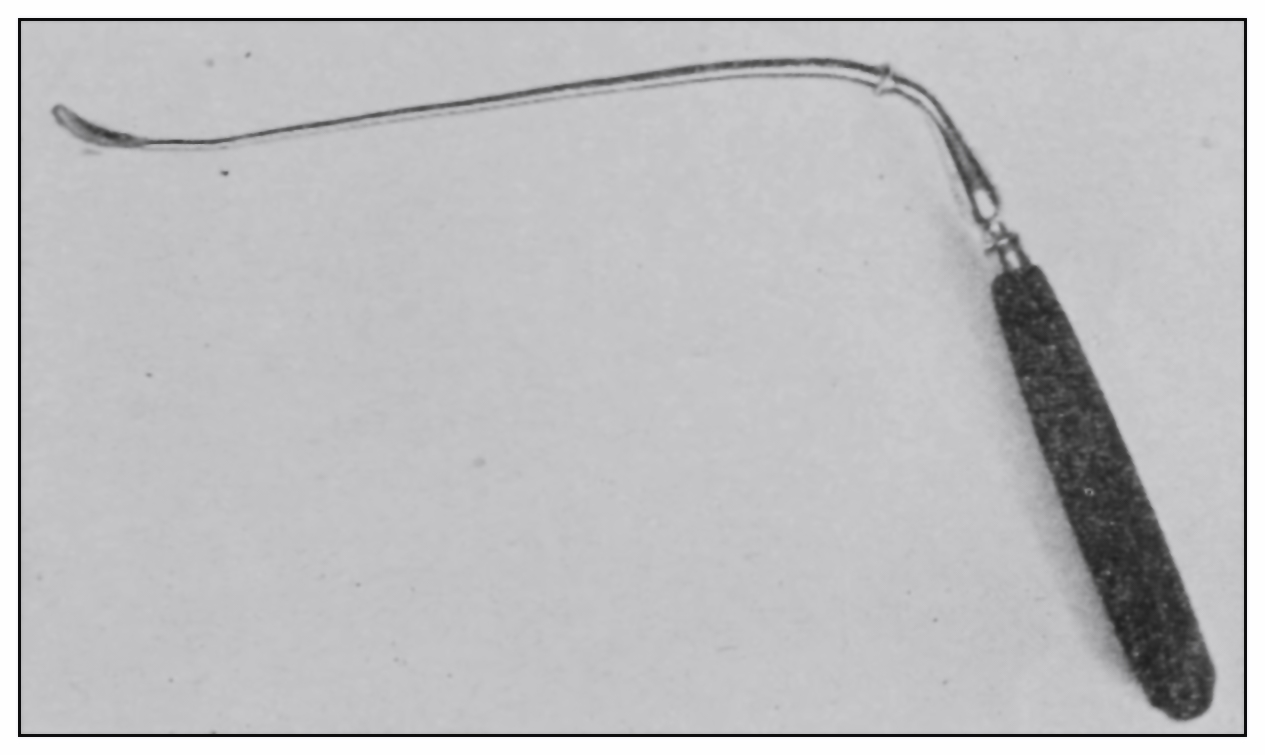

Fig. 17.—The hook for testing the valves.